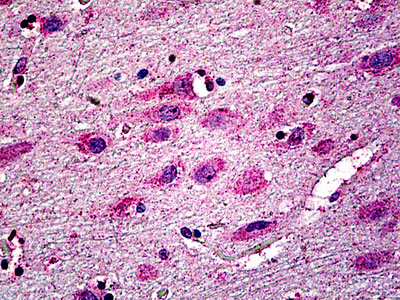

Anti-NMDAR2A antibody IHC of human brain, cortex.